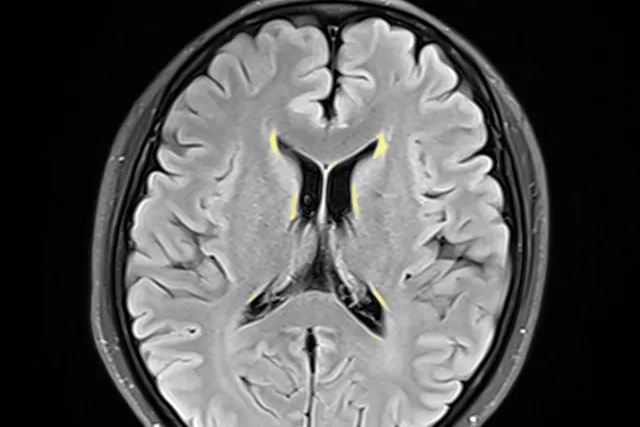

头痛头晕十余年,所谓「小病」也很折磨人!